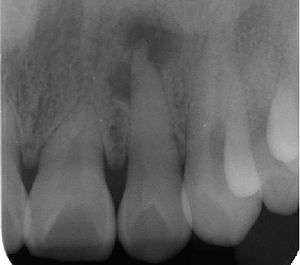

| Radiograph (X-ray) showing microdontia. Note also periapical lesion on the maxillary left lateral incisor. | |

Microdontia is a condition in which one or more teeth appear smaller than normal. In the generalized form, all teeth are involved. In the localized form, only a few teeth are involved. The most common teeth affected are the upper lateral incisors and third molars.

Localized microdontia is also termed focal, or pseudo-microdontia. A single tooth is smaller than normal.[3] Localized microdontia is far more common than generalized microdontia,[2] and is often associated with hypodontia (reduced number of teeth).[1] The most commonly involved tooth in localized microdontia is the maxiallry lateral incisor, which may also be shaped like an inverted cone (a "peg lateral").[3] Peg laterals typically occur on both sides,[2] and have short roots.[2] Inheritance may be involved,[2] and the frequency of microdontia in the upper laterals is just under 1%.[1] The second most commonly involved tooth is the maxillary third molars,[3] and after this supernumerary teeth.[3]